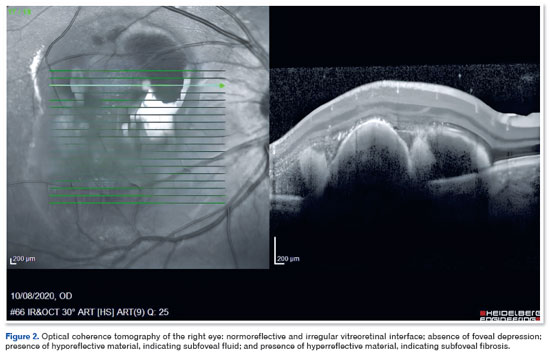

A 39-year-old man diagnosed with DM1 in early childhood (through a PCR test with capillary electrophoresis and Southern blot that detected pathological repeats of the CTG trinucleotide in DMPK) reported recent vision loss in the OD. On ophthalmologic examination, corrected visual acuity (CVA) was 20/100 in the OD and 20/20 in the OE. Biomicroscopy showed clear conjunctiva, transparent cornea, no reaction in the anterior chamber, and clear lens in both eyes. Extrinsic eye movement was preserved in both eyes. Retinal imaging showed subretinal hemorrhage in the macular area, associated with exudation in the OD (Figure 1). No retinal changes were observed in the OS. The findings of fluorescein angiography were hypofluorescence due to blockage in the macular area of the OD. Optical coherence tomography (OCT) revealed a normoreflective and irregular vitreoretinal interface, absence of foveal depression, presence of hyporeflective material indicating subfoveal fluid, and presence of hyperreflective material, suggesting subfoveal fibrosis (Figure 2).